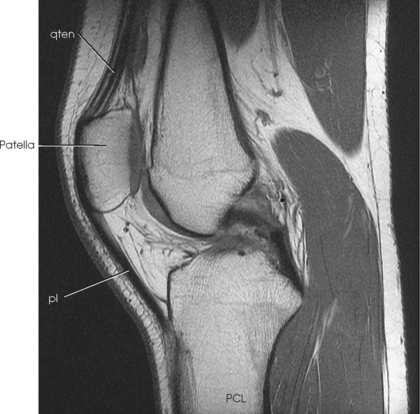

Structures shown: The resulting radiograph shows a lateral image of the distal end of the femur, patella, knee joint, proximal ends of the tibia and fibula, and adjacent soft tissue (Fig. 6-126).

Structures shown: The resulting image shows a lateral projection of the patella and patellofemoral joint space (Figs. 6-150 and 6-151).